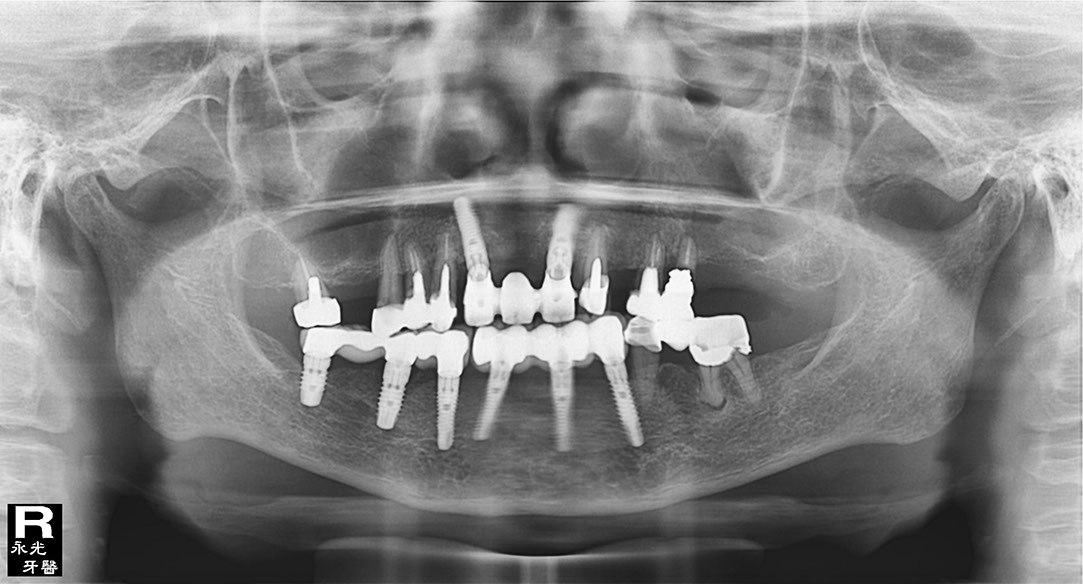

Implant 111d1.jpg

1113

光牙醫